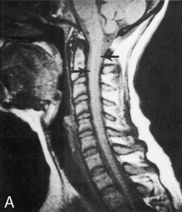

The cervical spine is relatively unstable and is still developing in young children. As a result, SCI patterns in children differ from those in adults. The ligaments along the child's cervical vertebrae are relatively lax, and the paraspinous muscles are incompletely developed. The child's vertebral bodies are wedge-shaped and not completely ossified. In addition, the facet joints of the cervical vertebrae are relatively flat. For these reasons, the vertebrae can shift several centimeters during injury or the application of force to the spine, resulting in spinal cord injury without evidence of injury to the vertebrae. Although the pediatric spine is relatively more elastic than the adult spine, it will be injured if significant cervical subluxation occurs (Fig. 11-19).

image image

Fig. 11-19 Spinal cord injury. Many injuries resulting in spinal cord damage produce visible radiographic changes, although a significant number (20%-60%) are not associated with any skeletal fracture or dislocation. A, Lateral cervical spine radiographs demonstrating skeletal abnormalities associated with cervical spine injury. The first radiograph is from a 4 year old who was restrained in a car seat that was not anchored in the car. The separation between the fifth and sixth cervical vertebrae is subtle but detectable (arrow), especially when compared with the line drawing of normal anatomy (far right). Radiopaque orogastric and nasogastric tubes are visible; they are slightly displaced anteriorly, indicating a small amount of edema surrounding the spinal cord injury. The location of the injury is unusual for this age. The second radiograph shows a 5-year-old pedestrian struck by an automobile and demonstrates significant separation between the first and second cervical vertebrae. This is a more common site of cervical spine injury in young children. Note the anterior displacement of the nasogastric tube (arrow) produced by edema surrounding the injury. An endotracheal tube is present but not visible. The line drawing depicts normal cervical spinal anatomy in a 3- to 4-year-old child. B, This scan film performed before a computed tomography scan demonstrates lumbar vertebral and spinal cord trauma associated with a lap belt injury. Separation of the lumbar vertebrae can be seen (arrow) and resulted in paraplegia. This injury resulted from flexion of the lumbar spine (see drawing). C, Flexion injury of the lower thoracic vertebrae and spine is visible on this anteroposterior chest radiograph. This radiograph shows an unrestrained 16-year-old driver who was thrown from the car. The lateral flexion resulted in compression of the spinal cord and fracture of the thoracic vertebrae (see arrow and corresponding illustration). The rod placed during surgery is visible. D, This magnetic resonance imagery scan shows in detail the skeletal and spinal damage resulting from a flexion-rotation injury. This 16-year-old motorcycle driver sustained displacement of two vertebrae (white arrows) and fracture of two vertebrae and one disc. Resulting compression of the cervical spine produced a complete spinal cord injury. A contusion is visible in the spinal cord (black arrow). The line drawing depicts the injury.

(A, courtesy Carol Gilbert and John Feldenzer, Roanoke, Va. Drawing reproduced from Riviello JJ, et al: Delayed cervical central cord syndrome after trivial trauma, Pediatr Emerg Care 6:116, 1990. B, courtesy Bennett Blumenkopf, Vanderbilt University Medical Center, Nashville, Tenn. Line drawing reproduced from Rudy EB: Advanced neurological and neurosurgical nursing, St Louis, 1984, Mosby. C, courtesy Noel Tulipan, Vanderbilt University Medical Center, Nashville, Tenn. Illustration reproduced from Rudy EB: Advanced neurological and neurosurgical nursing, St Louis, 1984, Mosby. D, courtesy Bennett Blumenkopf, Vanderbilt University, Nashville, Tenn. Line drawing reproduced from Rudy EB: Advanced neurological and neurosurgical nursing, St Louis, 1984, Mosby.)

Diagnostic Studies

Good quality cervical and thoracic lateral and anteroposterior radiographs will enable the detection of many spinal cord injuries (see Fig. 11-19).123 A lateral radiograph is obtained that includes the first cervical vertebra to the first thoracic vertebra.6 Occasionally the lateral displacement of vertebrae will be apparent on the anteroposterior radiograph and may be noted on the chest radiograph. If the radiographs are equivocal, or if nonvisualized SCI is suspected, flexion-extension radiographs are obtained after the child is alert and responsive.50

A CT scan will allow definitive visualization of the upper cervical spinal column, soft tissue, and vertebrae.50 This examination should be part of the CT scan performed for every child with a severe closed head injury.

MRI will provide beautifully detailed images of the spinal cord and all surrounding structures and tissues. Although these scans are not practical for the evaluation of unstable patients, they can be used during follow-up care (see Common Diagnostic Studies).